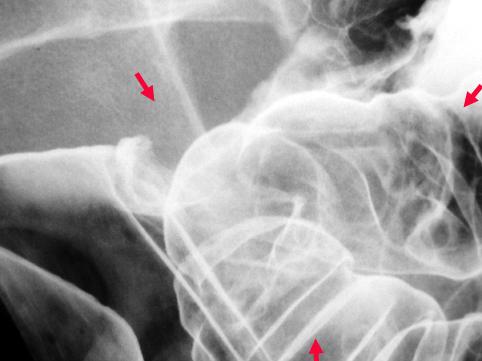

질환(병리주체)의 분류 악성 상피성종양/점액암

부위(장기별) 대장/직장

검사방법 X-P

종양의 육안분류 1형(종괴형)/

종양의 최대경(밀리미터) 40이상

종양의 심달도 ss(a1)